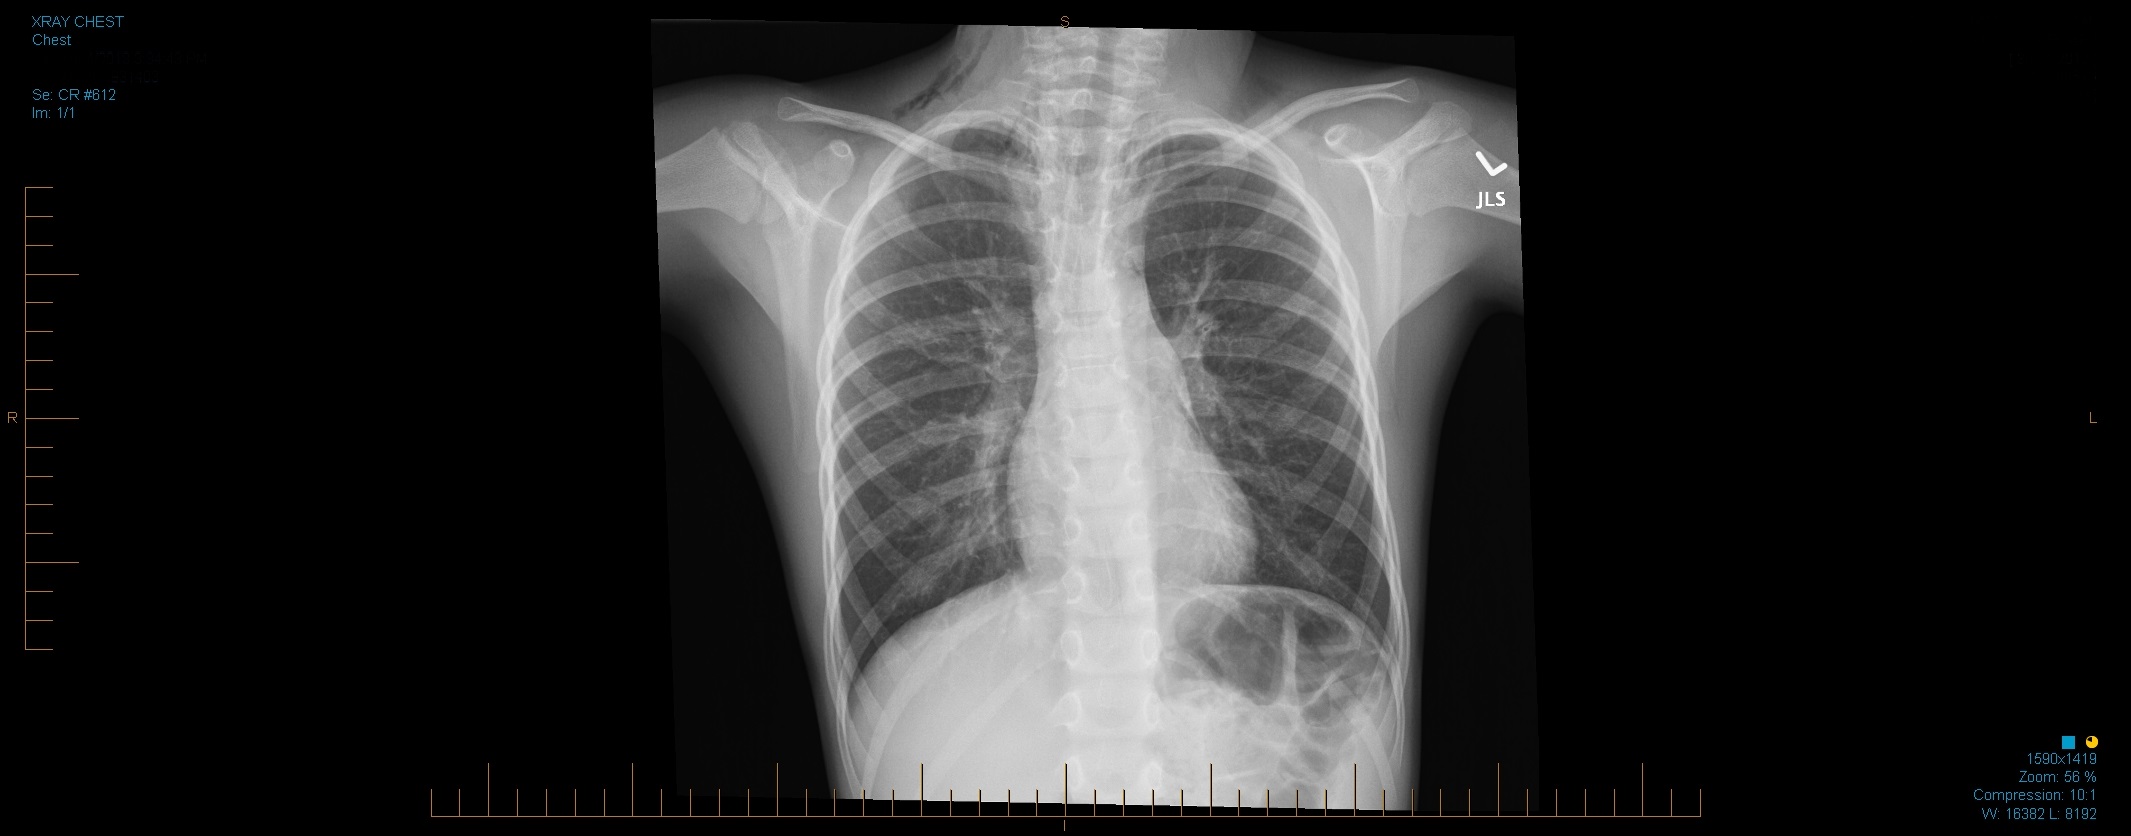

There is gas noted in the right side of the neck as well as the pneumomediastinum.

The lungs are clear. No effusion shown. Cardiac and mediastinal contours

are satisfactory. CT evaluation of the chest and neck could be considered if clinically indicated.